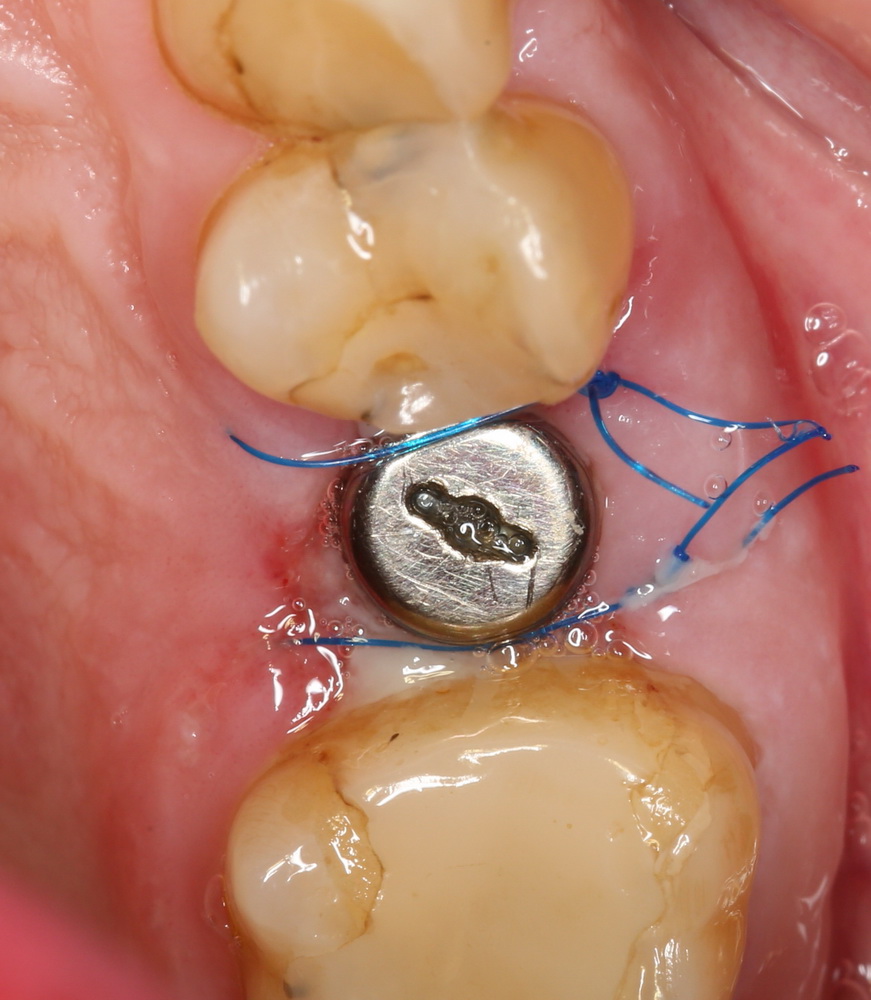

Но в данном случае стабильность хорошая, на имплантат фиксируем формирователь десны, накладываем швы:

Еще один важный момент. Не нужно пытаться стянуть рану и добиваться плотного прилегания десны к формирователю. Любое натяжение слизистой оболочки ведет к ее изменению (прикрепленная десна становится подвижной), а процессы атрофии костной ткани ускоряются. Чем меньше тянем и перемещаем — тем лучше. Поэтому вполне разумно оставить вокруг формирователя открытую рану шириной 0.5-1.5 мм, она нормально заживет вторичным натяжением.